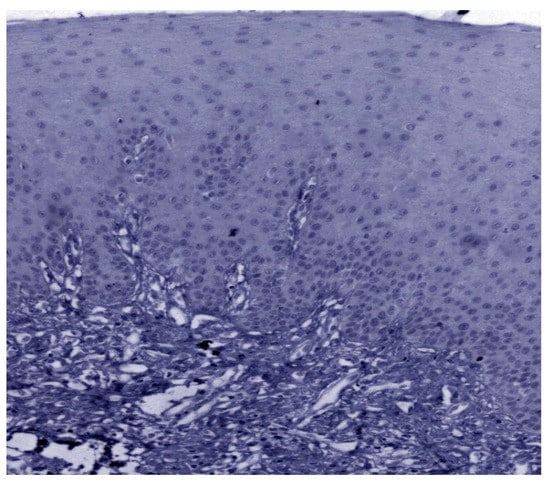

The expression of 14-3-3ε was studied in 130 patients, of which 81.5% (106/130) were found to be expressing 14-3-3ε. There was a significant correlation (p = 0.000; χ2 = 33.600) with expression among normal vs. OSMF vs. OSMF vs. OSCC patients. Table 4 shows the details of 14-3-3ε expression, which correlated with clinicopathological parameters. We found a statistically significant overexpression (p = 0.019; χ2 = 5.496) with increased age (>43 years), atrophic epithelium (p = 0.011; χ2 = 13.149) and increased degrees of inflammation (p = 0.041; χ2 = 8.252). Figure 7 shows the negative immunoexpression of 14-3-3ε in normal samples. Figure 8 shows the 14-3-3ε-positive immunoexpression in epithelial cells in OSMF samples, with cytoplasmic and nuclear positivity. In OSCC samples, 14-3-3ε demonstrates strong cytoplasmic and nuclear positivity in malignant epithelial cells (Figure 9).

Figure 7.

IHC for 14-3-3ε in normal samples (under 20× magnification).

Figure 8.

IHC for 14-3-3ε in OSMF samples (under 20× magnification).